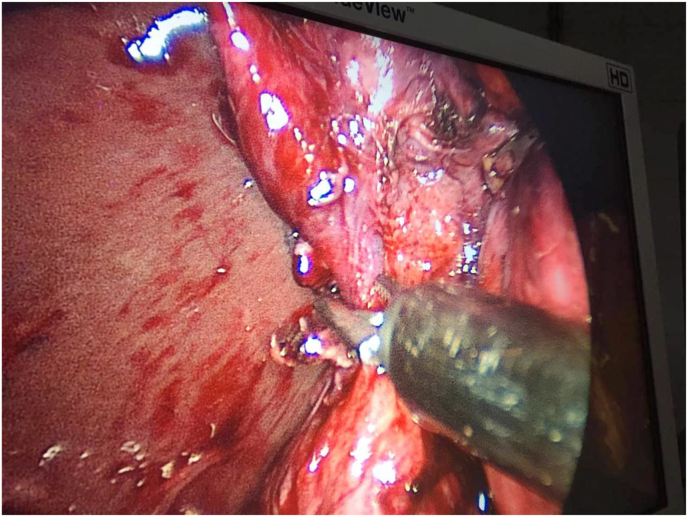

Laparoscopic surgery was performed, in which the cystic duct and artery were isolated(Fig. 1). dissection of the gallbladder revealed a ruptured hydatid cyst and the germinal layer was recognized(Fig. 2).